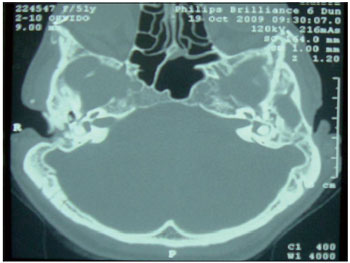

CASE REPORTCASE 1: S.A.T. was a 52-year-old woman who complained of bilateral hearing loss since birth and had been diagnosed with Treacher-Collins syndrome. Physical examination showed atresia of the EAC. Audiometry showed mixed hearing loss, and computed tomography showed severe bilateral temporal bone atresia at the EAC without changes in the middle or inner ear. (Figure 1) The patient had used a tiara-type bone contact device for 10 years but had recently noted worsening in her hearing. After jointly assessing the case with speech therapists and obtaining the patient's consent, the clinicians opted for a BAHA® implant in the left mastoid. The surgical procedure was performed via a vertical incision technique and was uneventful. (Figure 2) One late complication occurred in that skin grew over the titanium implant; this was solved by simple resection in the doctor's office. A 4-month period was allowed for osseointegration. The patient states that she is satisfied with the results and has noted significant improvement in her work and in everyday activities such as watching television, talking with friends, answering calls, and listening to music. She uses the prosthesis 12 hours per day with the drawback that the battery life is short (13 days). The audiometric results obtained with the use of the prosthesis showed a postoperative reduction in the speech reception threshold (SRT) by 35 dB and a speech recognition rate of 65% at 92 dB (Figure 4).

Figure 1. Computed tomography of the temporal bone, axial section, showing atresia of the external auditory canal.